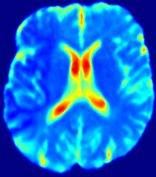

4.3.1 Advection Imaging via Advection-Diffusion

Slice #1Slice #2Slice #3Slice #4Slice #5Slice #6𝐕gt𝟐subscriptnormsuperscript𝐕gt2\|\bf{V}^{\text{gt}}\|_{2}Refer to captionRefer to captionRefer to captionRefer to captionRefer to captionRefer to caption𝐕est𝟐subscriptnormsuperscript𝐕est2\|\bf{V}^{\text{est}}\|_{2}Refer to captionRefer to captionRefer to captionRefer to captionRefer to captionRefer to captionRefer to caption1.51.51.51.21.21.20.90.90.90.60.60.60.30.30.30.00.00.0(mm/s)𝑚𝑚𝑠(mm/s)Destsuperscript𝐷estD^{\text{est}}Refer to captionRefer to captionRefer to captionRefer to captionRefer to captionRefer to captionRefer to caption0.0150.0150.0150.0120.0120.0120.0090.0090.0090.0060.0060.0060.0030.0030.0030.0000.0000.000(mm2/s)𝑚superscript𝑚2𝑠(mm^{2}/s)

Figure 14: PIANO identifiability testing: advection imaging via advection-diffusion. Top row shows 𝐕gt2subscriptnormsuperscript𝐕gt2\|{\bf{V}}^{\text{gt}}\|_{2} used for simulating ground truth pure advection. Rows below show the estimated 𝐕est2subscriptnormsuperscript𝐕est2\|{\bf{V}}^{\text{est}}\|_{2} and Destsuperscript𝐷estD^{\text{est}} on corresponding slices. Note that the plotted value scale for Destsuperscript𝐷estD^{\text{est}} is 0.01 of that for 𝐕gt2subscriptnormsuperscript𝐕gt2\|{\bf{V}}^{\text{gt}}\|_{2} and 𝐕est2subscriptnormsuperscript𝐕est2\|{\bf{V}}^{\text{est}}\|_{2}.

We use the same ‘Advection Imaging’ simulation of Sec. 4.2.1 as the concentration dataset for PIANO. However, instead of modeling pure advection (Eq. 15), we let PIANO estimate both velocity 𝐕estsuperscript𝐕est{\bf{V}}^{\text{est}} and diffusivity Destsuperscript𝐷estD^{\text{est}} via the advection-diffusion PDE (Eq. 2) underlying the proposed PIANO model. Fig. 14 shows the estimated 𝐕est2,subscriptnormsuperscript𝐕est2\|{\bf{V}}^{\text{est}}\|_{2}, and Destsuperscript𝐷estD^{\text{est}} fields for one patient. Although PIANO has the freedom to estimate both a velocity and a diffusivity field from pure advection, PIANO differentiates well between advection and diffusion: the estimated 𝐕est2subscriptnormsuperscript𝐕est2\|{\bf{V}}^{\text{est}}\|_{2} successfully reproduces the ground truth 𝐕gt2subscriptnormsuperscript𝐕gt2\|{\bf{V}}^{\text{gt}}\|_{2} governing the simulated advection process, just as it already did in the ‘Advection Imaging via Advection’ test (Fig. 12). More importantly, the estimated diffusivity Destsuperscript𝐷estD^{\text{est}} is orders of magnitudes smaller than 𝐕est2subscriptnormsuperscript𝐕est2\|{\bf{V}}^{\text{est}}\|_{2}, indicating the estimated diffusion is negligible compared to the estimated advection, which is highly consistent with the underlying pure advection of the simulated data.